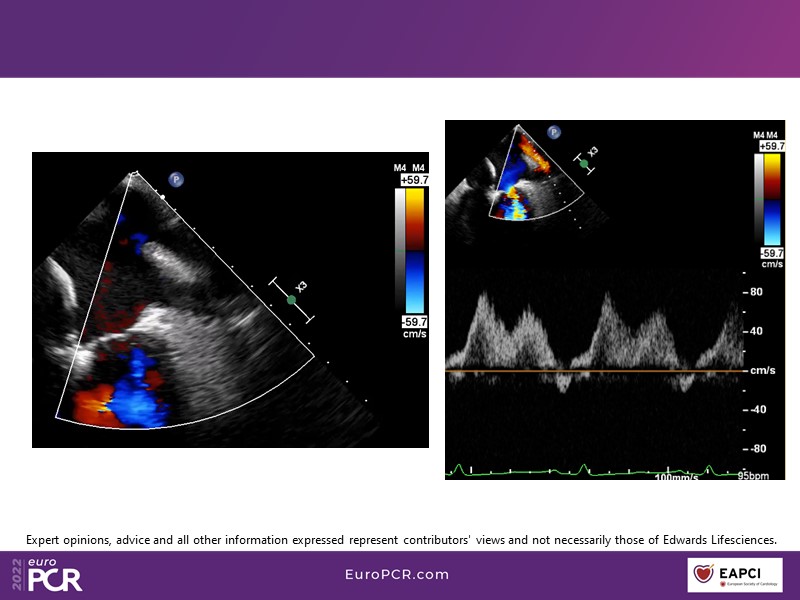

With study outcomes and clinical cases, this EuroPCR 2022 session will enable you to discuss the anatomical considerations that define suitable candidates for treatment of mitral regurgitation with the PASCAL platform and highlight key differentiators and tips and tricks for its use.

- To discuss which anatomical considerations define suitable candidates for the treatment of mitral regurgitation with the PASCAL platform

- To attend case-based discussions that will highlight key differentiators and tips and tricks when using the PASCAL platform to treat mitral regurgitation